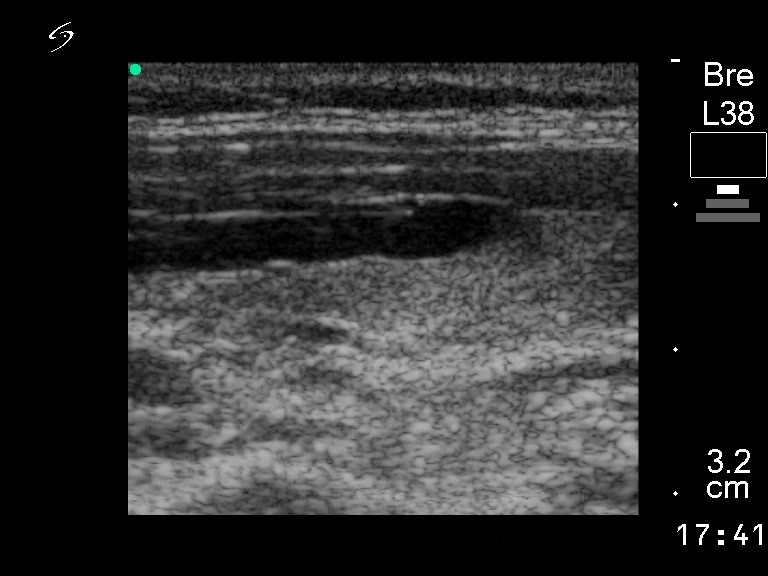

Other edifying cases - Case 7: Identifying a vessel in unusual localization within the thyroid |

Clinical presentation: a 48-year-old woman with a "nodule" discovered on sonographic screening was referred for an evaluation.

Ultrasonography: normal thyroids with a vessel in unusual location within the thyroid.

Final report: the thyroid is healthy.